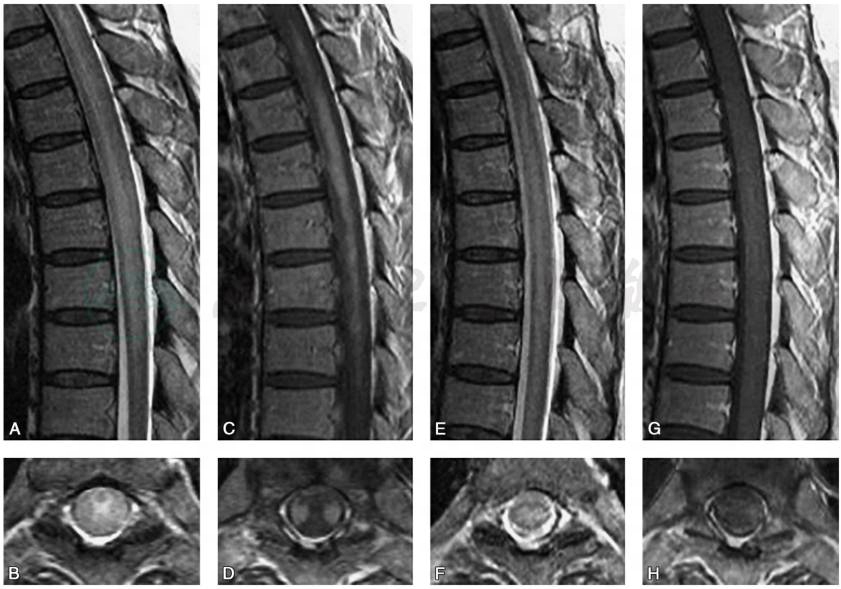

脑CT多无异常。MRI检查可见大脑半球深部脑室周围白质散在的大小不等斑片状异常信号灶,T1WI呈均匀低信号,T2WI为明显高信号,无明显占位效应,少数病例脑干、小脑有异常信号,受累脊髓节段变细(Morgan,2007)(图1)。脊髓MRI出现T2WI高信号,提示HAM/TSP为快速进展期,临床表现为严重的运动功能受累(Yukitake,2008)(图2),MRI检查正常并不能除外HAM/TSP。

图2患者女性,58岁,发病12个月后脊髓MRI检查

A.T2WI矢状位可见脊髓中央部高信号;B.与A对应的轴位像;C.Gd-DTPA增强后矢状位的T1WI;D.与C对应的轴位像,可见T4~T9双侧皮质脊髓束增强;E、F.治疗后3周的T2WI矢状位及其对应的轴位像;G、H.Gd-DTPA增强后矢状位及其对应的轴位像,可见治疗后增强的病灶消失

引自:神经病学:全2册.第3版.ISBN:978-7-117-31406-0.主编: